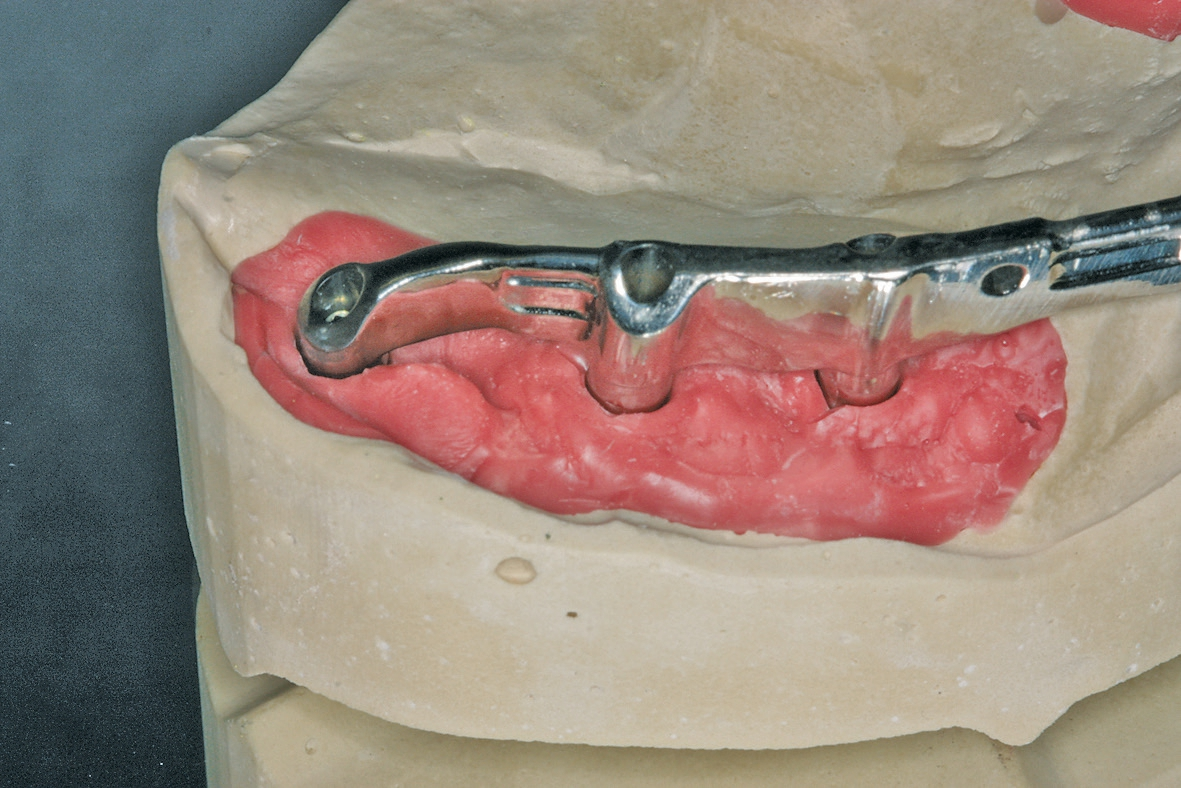

Zurück im Labor wurde der fertige Steg bei perfekter Passung auf dem Meistermodell verschraubt und in der nächsten Sitzung anprobiert (Abb. 16a u. b).

Die besondere zahntechnische Herausforderung bestand nun darin, das Implantat über ein Abutment in die vorhandene Stegversorgung einzubeziehen. Die genaue Position wurde über eine Abformung mit Laboranalogen bestimmt, kontrolliert durch ein OPG (Abb. 21). Wieder wurde in situ mit einem Übertragungsschlüssel aus Pattern gearbeitet, um das neu zu fertigende Stegstück spannungsfrei anschließen zu können. Nach ausgiebigen Prüfungen wurde die Ergänzung gegossen und nach der Patientenanprobe an den bestehenden Stegbogen angelasert (Abb. 22a u. b, Abb. 23). Es folgte die Herstellung der endgültigen Sekundär- und Tertiärstruktur (Abb. 24). Bei dem hier vorgestellten Patientenfall wurde das Sekundärgerüst herkömmlich gegossen (Brealloy, Bredent, Senden). Lichthärtender Kunststoff sowie Konfektionszähne komplettierten die Arbeit, wobei die Ästhetikanprobe unverändert übernommen wurde.